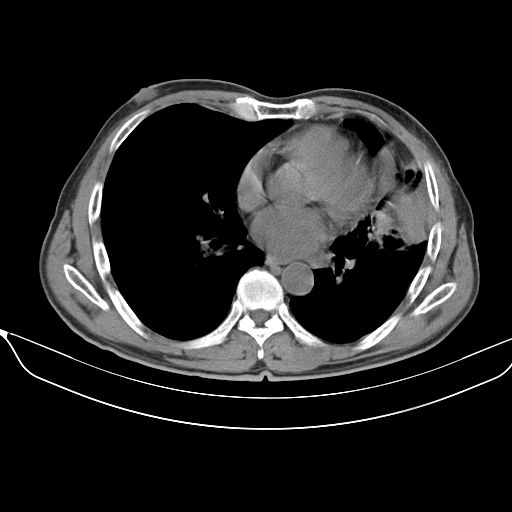

以下是引用心路寻觅在2010-3-1 10:23:00的发言:[br]1、考虑左肺上叶周围型肺癌[br]2、右上肺陈旧性病灶。[br][br][本贴已被 心路寻觅 于 2010-3-1 10:40:18 修改过]

以下是引用shuiyuan在2010-3-1 10:45:00的发言:[br]考虑左肺上叶中心型肺癌伴阻塞型炎症,邻近胸膜受侵。